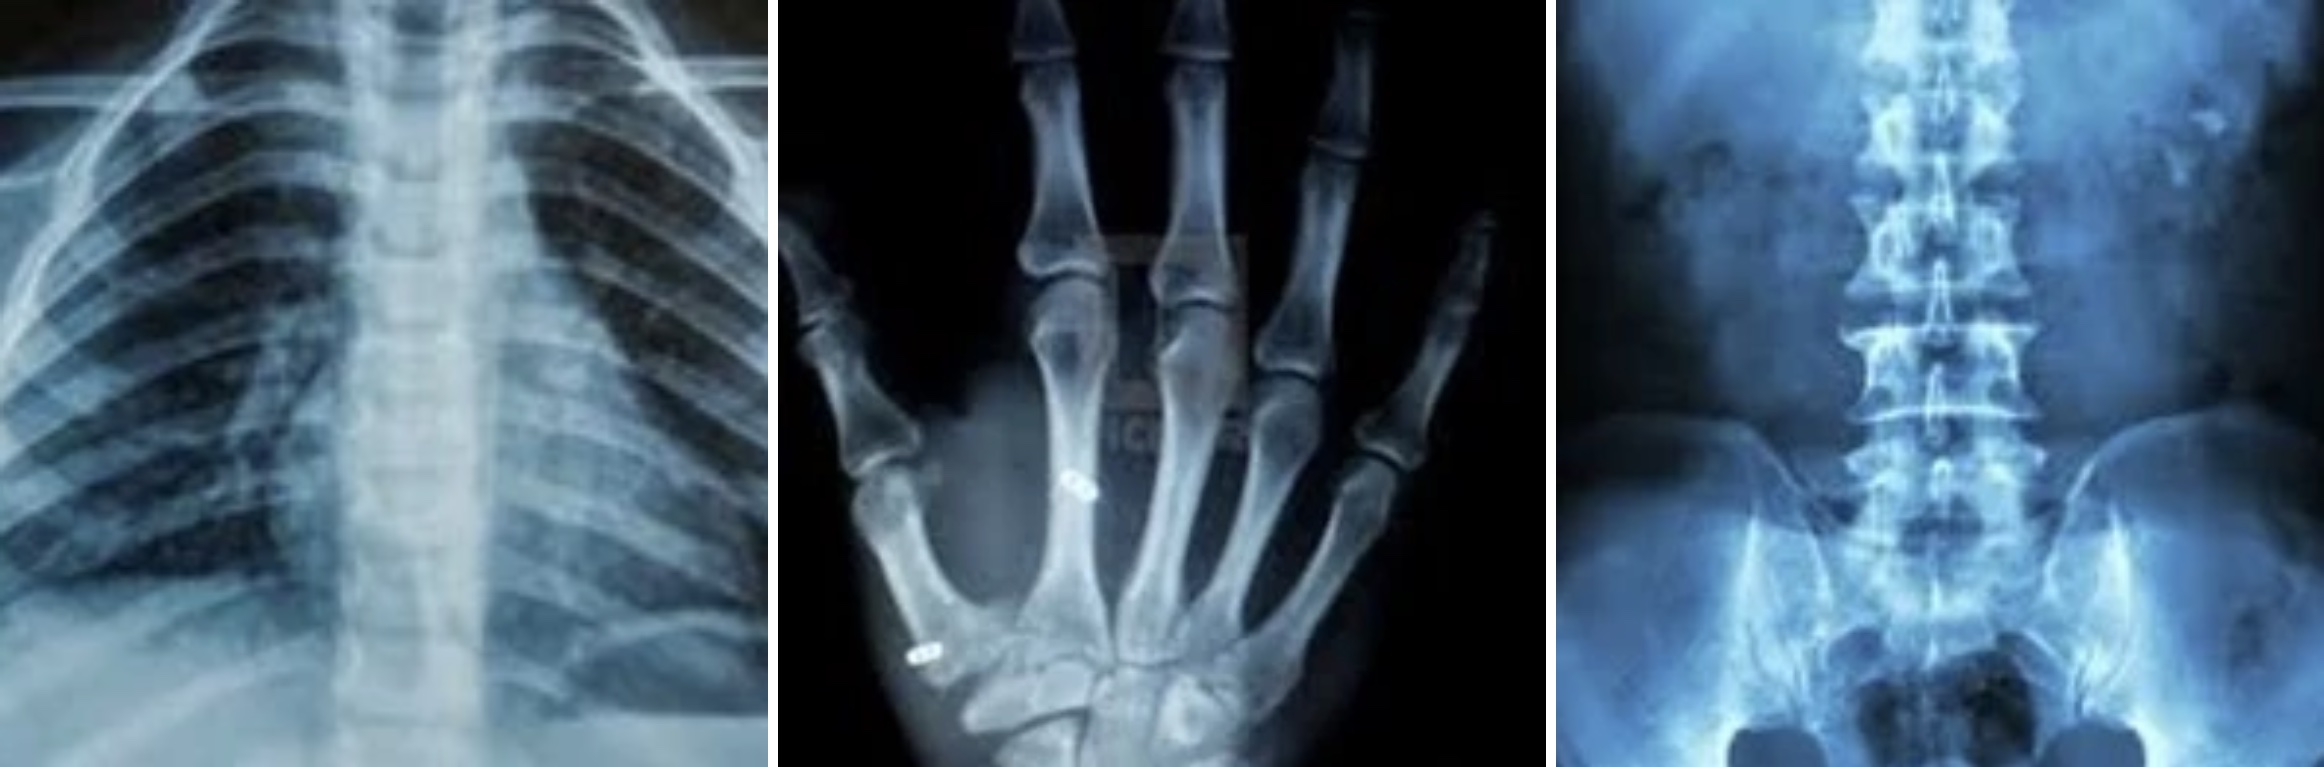

An X-ray is a quick, painless test that produces images of the structures inside your body — particularly your bones.

X-ray beams pass through your body and are absorbed in different amounts depending on the density of the material they pass through. Dense materials, such as bone and metal, show up as white on X-rays. The air in your lungs shows up as black. Fat and muscle appear as shades of grey.

X-ray is done on many areas of the body.

Bones and Teeth

Fractures and infection: In most cases, fractures and infections in bones and teeth show up clearly on X-rays.

Arthritis: X-rays of your joints can reveal evidence of arthritis. X-rays taken over the years can help your doctor determine if your arthritis is regressing.

Osteoporosis: Special types of X-ray tests (BMD tests) can measure your bone density.

Bone cancer: X-rays can reveal bone tumors.

Chest

Lung infections or conditions: Evidence of pneumonia, tuberculosis or lung cancer can show up on chest X-rays.

Enlarged heart: This sign of congestive heart failure shows up clearly on X-rays.

Abdomen

Swallowed item: If your child has swallowed something such as a key or a coin, an X-ray can show the location of that object.